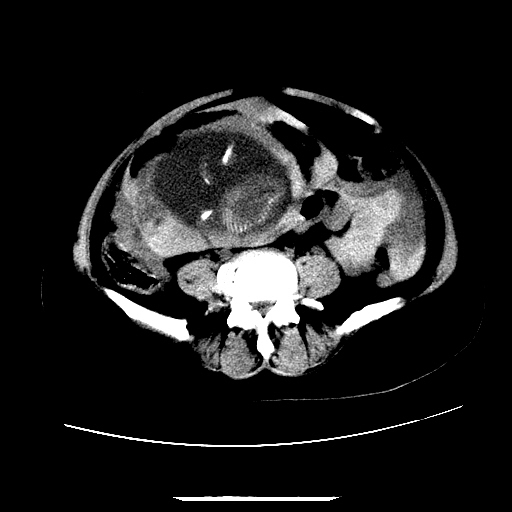

f,45y.怀孕4月晕倒,b超提示死胎,有手术结果,请展开讨论后明天告诉。

膈下-肠间隙内见气体密度影,子宫轮廓显示不清,宫腔-腹腔积液,首选考虑---子宫破裂出血。

1)宫腔妊娠。2)子宫破裂出血,腹腔及盆腔积血。

感谢同行们的高见。手术结果:子宫破裂出血。

我们的诊断是:腹、盆腔积液(考虑腹盆腔脏器破裂出血);宫腔妊娠。让人纳闷的是当时我们没有经验,现在回头看看分析:4月宫腔妊娠:1、洋膜囊不可能紧贴胎体这么小;2仔细看看子宫后壁肌层模糊不清;3腹、盆腔液体来源原因?4、45岁高龄妊娠有晕倒。由此可大胆诊断:宫腔妊娠子宫破裂出血。